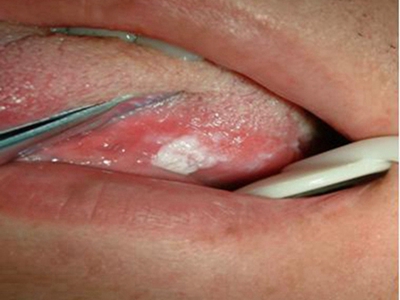

舌侧

白斑

口腔白斑病舌头颗粒状白斑图

口腔白斑病表现为舌头表面出现颗粒状白斑,患处呈红白相间状,白色颗粒状突起于皮肤,稍硬,黏膜表面不平坦,似有小片状或点状糜烂。